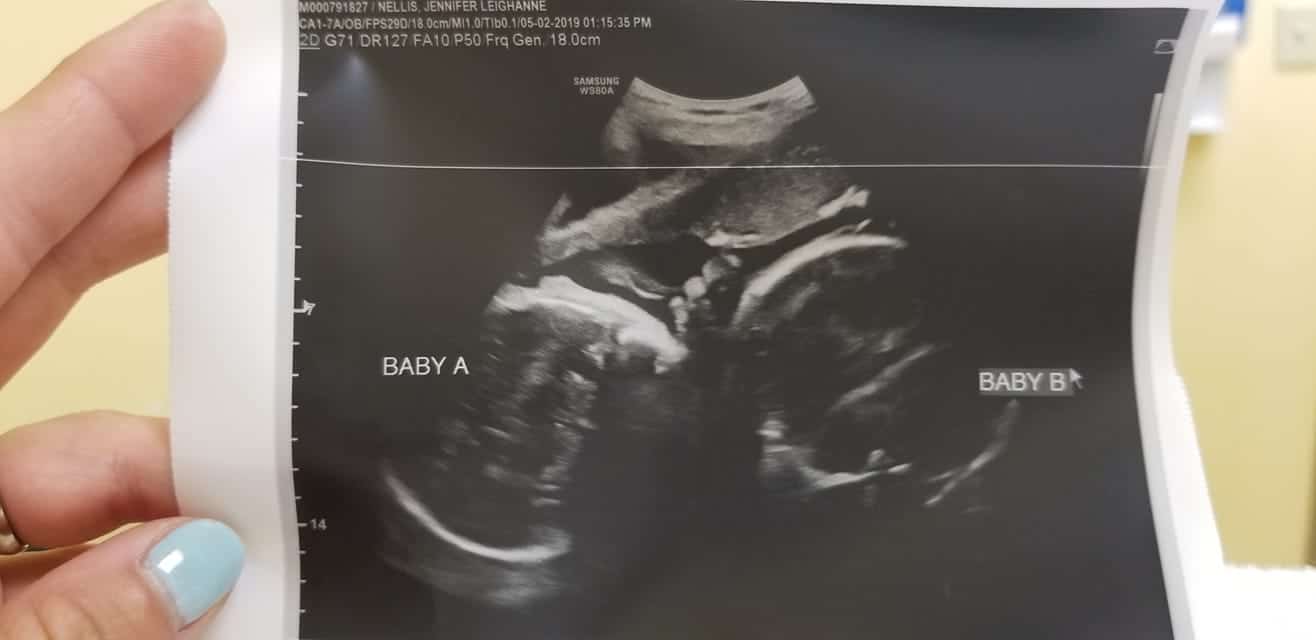

- Ultrasound Photos at 35 Weeks Pregnant With Twins

Ultrasound Photos at 35 Weeks Pregnant With Twins